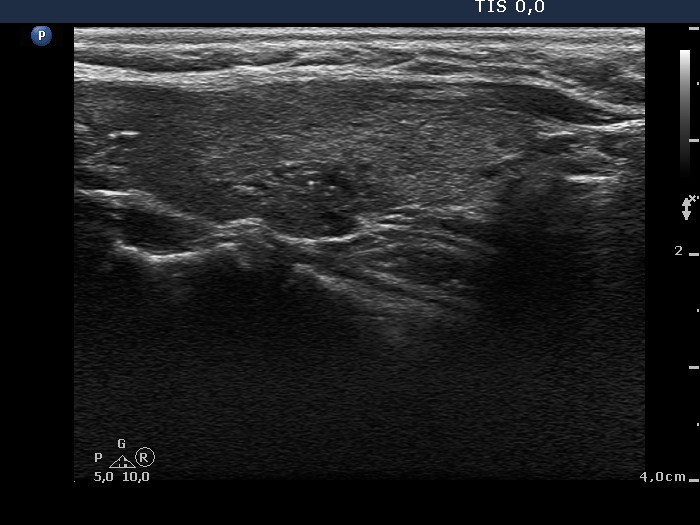

Ultrasonography: The thyroid was hypoechogenic. There was a small, more hypoechogenic area with blurred borders and a focus of microcalcification in the left thyroid.

Cytology was performed from the lesion in the left lobe and resulted in Hashimoto's thyroiditis.